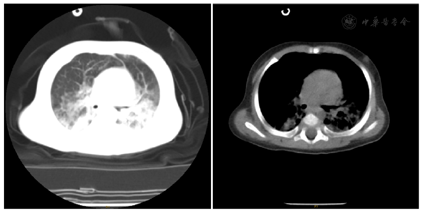

血常规:WBC 13.2×109/L,N 73.7%,HGB 106 g/L,PLT 762×109/L,CRP 9 mg/L。CRP 52 mg/L,PCT 2.13 ng/ml。肝肾功:ALT 47 U/L,AST 58 U/L,TB 0.7 umol/L,ALB 30.5 g/L,LDH 731 U/L,余值大致正常。血气分析:PH 7.340,PCO2 6.0 kPa,K+ 3.22 mmol/L,LAC 2.1 mmol/L,GLU 9.0 mmol/L,余值正常。心肌酶谱未见异常。DIC筛查:DDI 1.22 mg/L,Fg 157 mg/dl,TT 21.5 s,余值正常。胸部CT:双肺感染,有明显渗出和实变及肺间质改变,可见局限性肺气肿;双侧胸膜增厚,右侧胸腔少量积液;双侧肺门显示欠清晰,气管前腔静脉后淋巴结稍显偏大(图1)。多次痰培养:查见革兰阳性球菌、革兰阴性球菌/混合菌丛。呼吸道病毒七联检:呼吸道合胞病毒抗原阳性,其余均阴性。肺炎支原体+衣原体核酸:阴性。体液免疫:IgG 8.5 g/L(输注丙球后),IgA<0.07 g/L,IgM 0.51 g/L,IgE<5 IU/ml。细胞免疫:CD3 2%~3.3%,CD4 0.9%~1.8%,CD8 0.3%~0.4%,CD4/CD8 2.3~6,B淋巴细胞95.5%~95.9%,NK细胞0.6%~0.7%。输血免疫全套:HBsAb、HBeAb、HBcAb阳性,其余均阴性。大便常规未见异常。小便常规:酮体1+,余未见异常。

患儿为男性,起病急,病程长,临床主要表现为重症肺炎。呼吸道合胞病毒阳性,T淋巴细胞检查CD3、CD4、CD8均显著减低,NK淋巴细胞显著降低,B淋巴细胞虽比例增高,但体液免疫显著减低(IgA<0.07 g/L),回顾胸部CT可见胸腺影小,结合家系全外显子测序分析查见IL2RG基因c.1A>T可能致病性突变,故诊断为X-连锁重症联合免疫缺陷病。